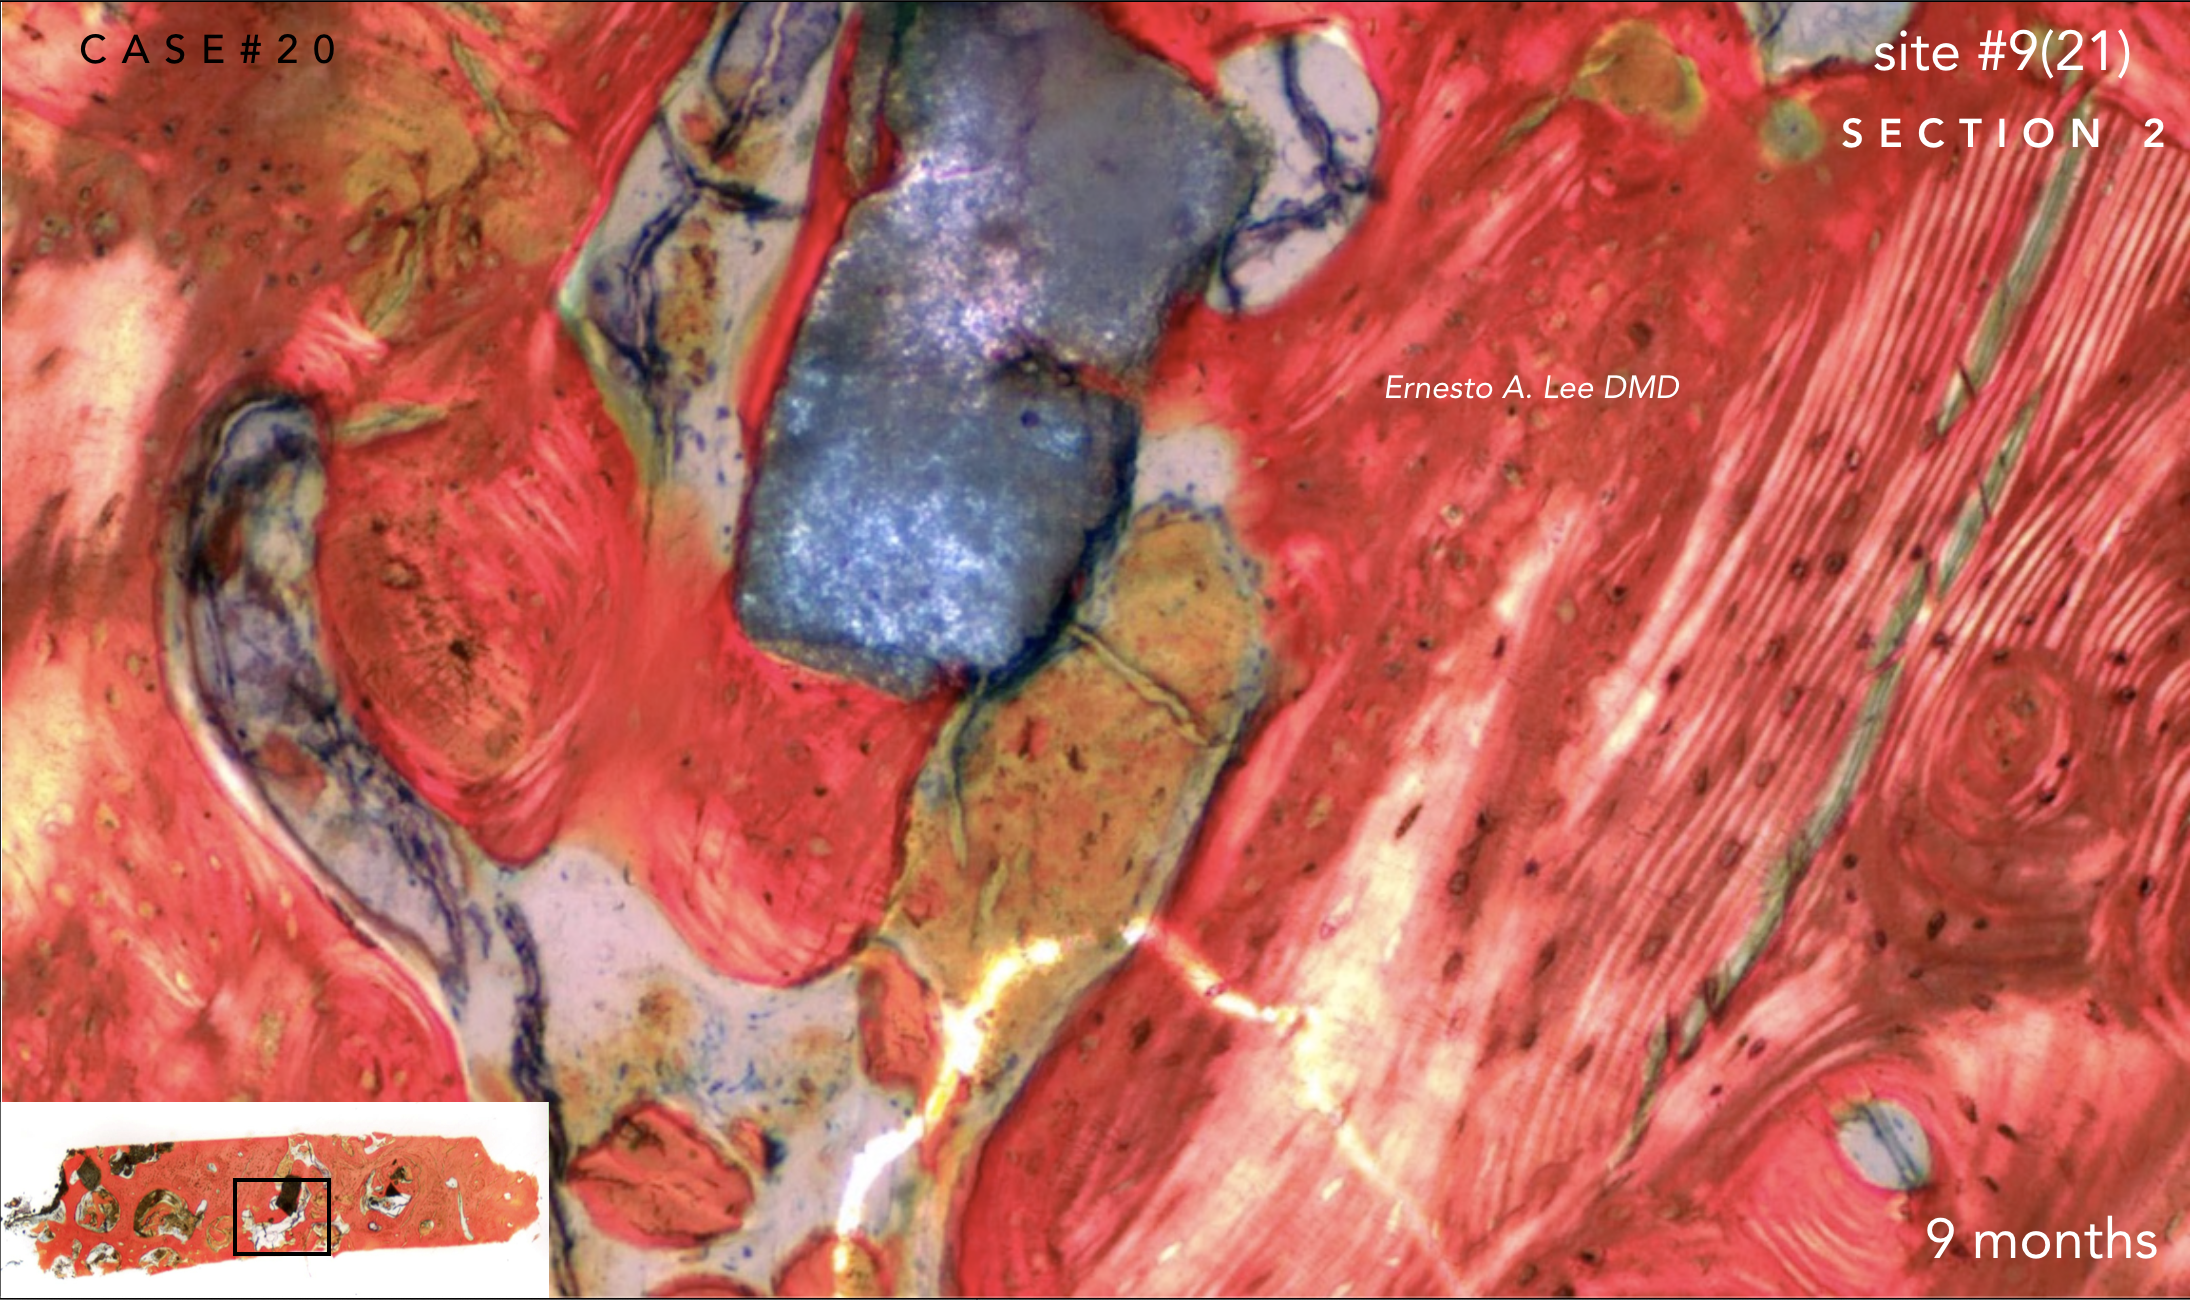

With the patient’s consent, a core specimen was harvested during the osteotomy preparation for implant #9(21) and sent for histologic analysis.

The interstitial and concentric lamellar bone patterns observed are consistent with the appearance of healthy, orderly, living bone.

With the patient's authorization, a specimen was harvested during the osteotomy preparation for implant on site #9(21) and sent for histologic analysis.